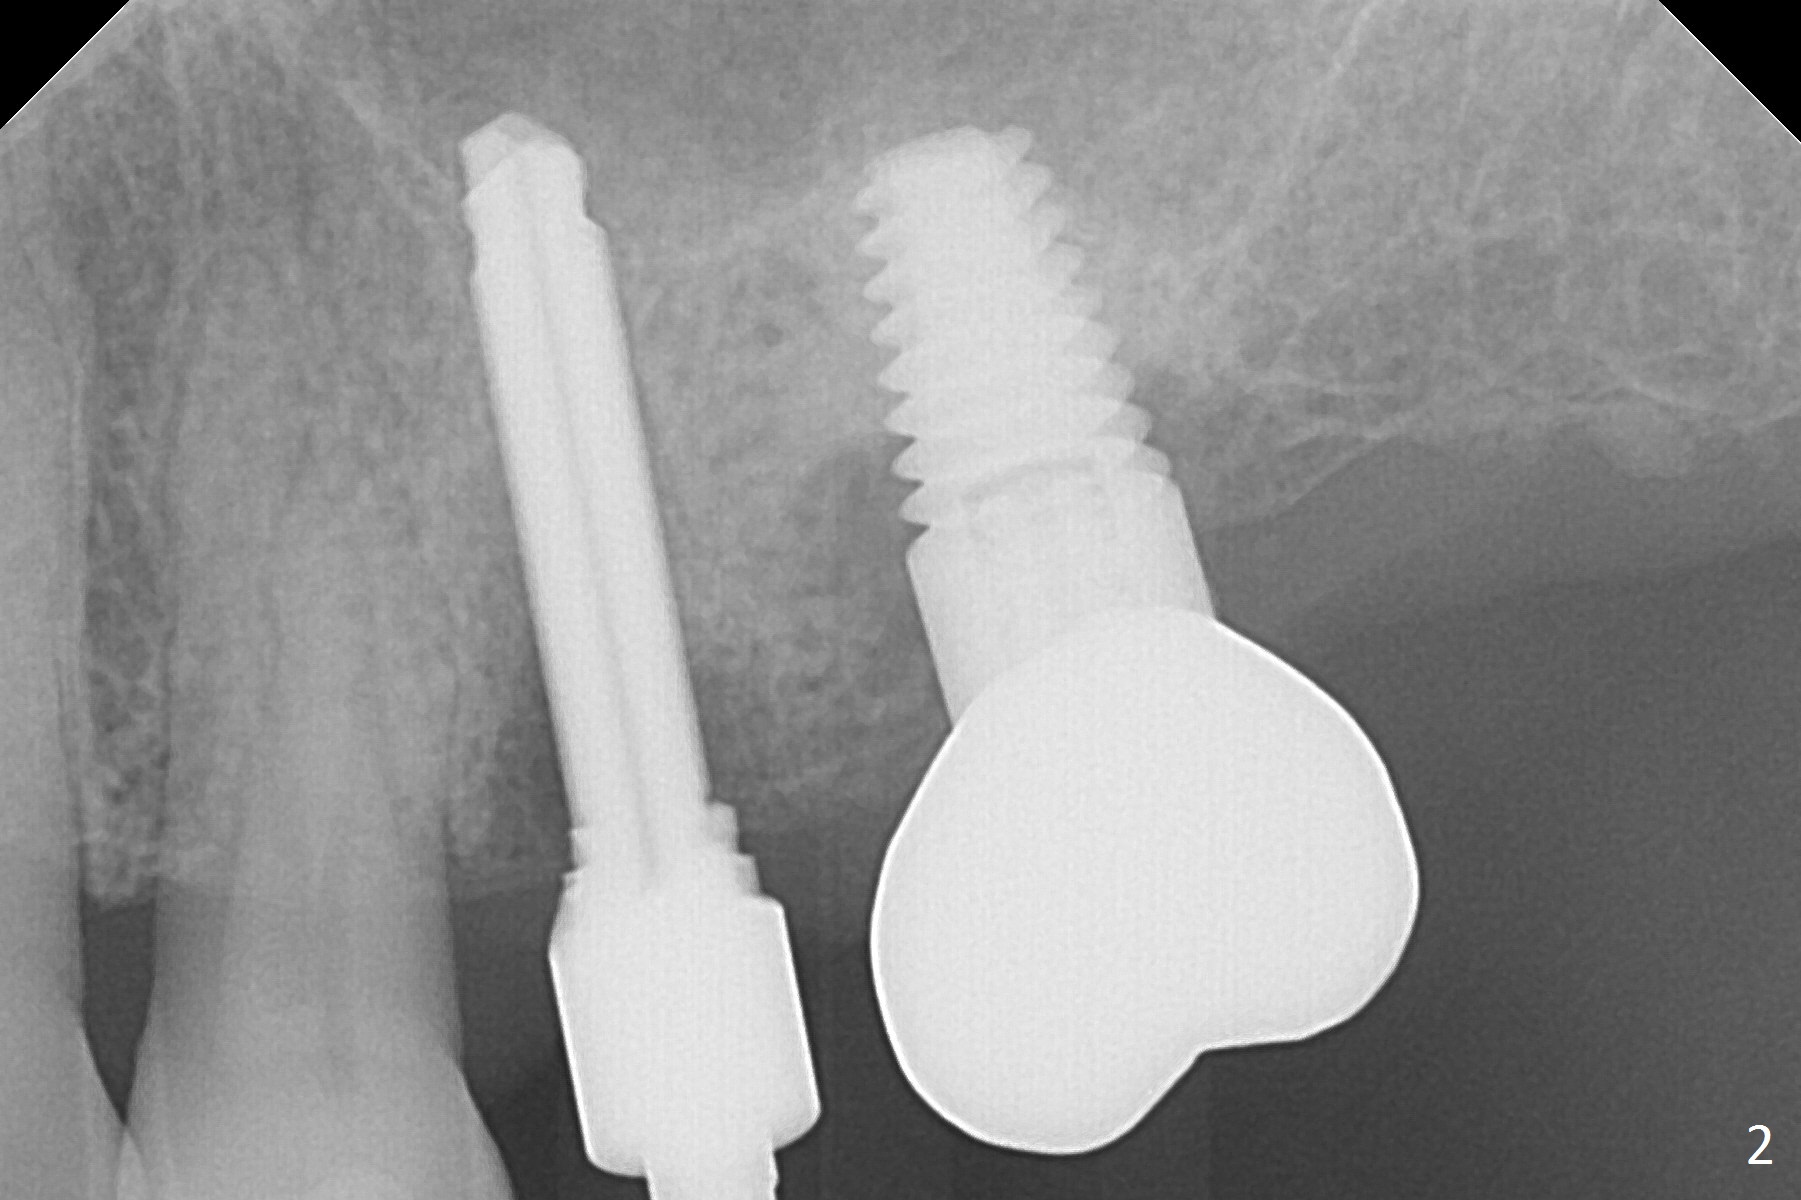

A Linderman bur is used to move the initial osteotomy distal. By the time of 3 mm in place, the trajectory seems to have improved; the sinus floor has been penetrated (Fig.2). Retrospectively, the parallel pin is not as sharp as the 2 mm drill to penetrate the perforated sinus floor (Fig.1).

After placement of allograft in the sinus (Fig.3 <), a 4x11.5 mm UF implant is placed with 45 Ncm. Following bone graft placement in the buccal gap, Osteogen tape lingually and insertion of a 4.5x4(3) mm abutment, an immediate provisional is fabricated.